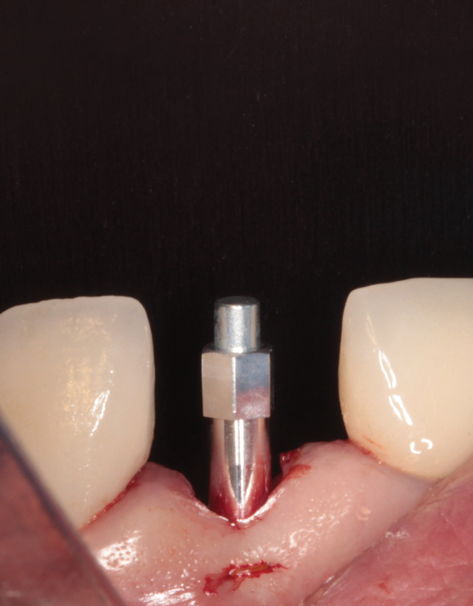

(35.) An implant being inserted into the prepared osteotomy of a patient who presented for the replacement of the maxillary left central incisor.

Figure 35

(36.) The implant’s primary stability was assessed by RFA, and the ISQ value greater than 65 was used to determine that immediate provisionalization was indicated.

Figure 36

(37.) The implant’s primary stability was assessed by RFA, and the ISQ value greater than 65 was used to determine that immediate provisionalization was indicated.

Figure 37